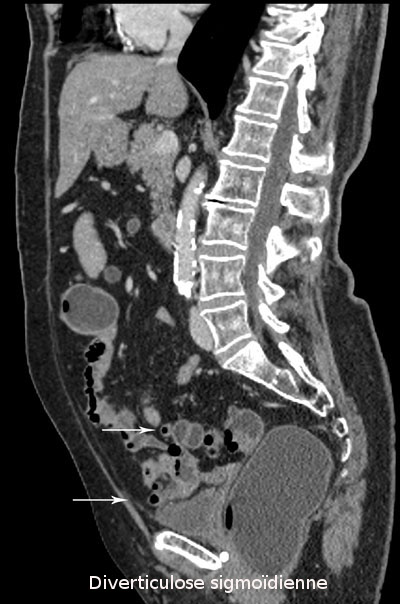

Lésion villeuse du segment distal du sigmoïde (images 1, 2 et 3)